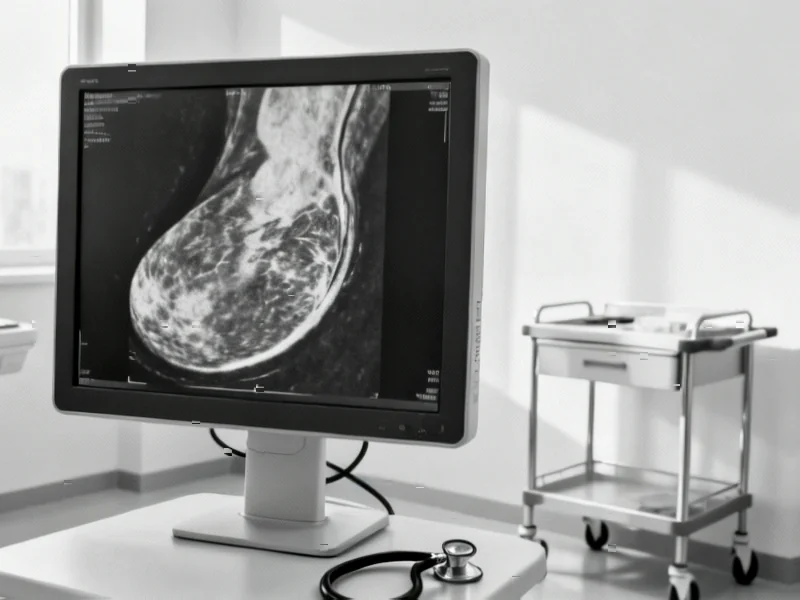

According to Nature, researchers have developed a novel deep learning approach that significantly improves breast cancer detection accuracy in mammograms. The study employs a Bacterial Foraging Optimization (BFO) algorithm to automatically tune hyperparameters in convolutional neural networks, achieving accuracy improvements of 7.62% for VGG 19, 9.16% for InceptionV3, and 1.78% for a custom CNN-20 layer model. Using the Digital Database for Screening Mammography dataset, the system optimizes critical parameters like filter size, number of filters, and hidden layers to enhance detection of subtle abnormalities in mammogram images. Given that breast cancer affected over 2.3 million people and caused 685,000 deaths in 2020, this automated approach addresses the critical need for more accurate early detection methods. This breakthrough represents a significant advancement in medical AI applications.